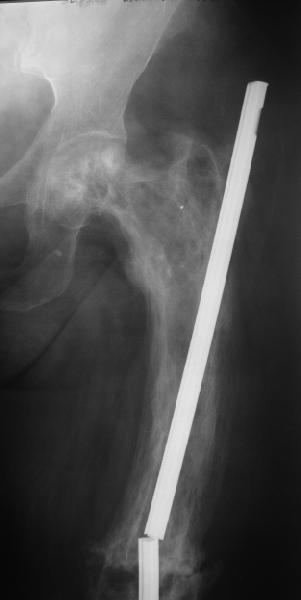

Еще один пример. Пациентка с юга России, прислала рентгенограммы через

год. На сегодня прошло 2 г. 8 мес. после операции. Несмотря на не очень

убедительный процесс сращения, пациентка ходит. Учитывая остеопороз при

Педжете, решили, что динамизировать вообще не нужно.